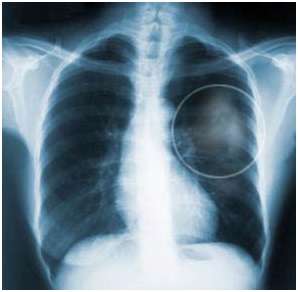

Остаточные посттуберкулезные изменения легких у взрослых

Остаточные изменения в легких после туберкулеза могут сохраняться в течение всей жизни. Функциональное состояние дыхательной системы часто нарушается, что приводит к недостаточному снабжению кислородом всех органов. Во избежание развития осложнений и снижения качества жизни необходимо обращать внимание на клинические симптомы и проходить периодические осмотры у фтизиатра, частота которых зависит от типа посттуберкулезных явлений. Виды остаточных …